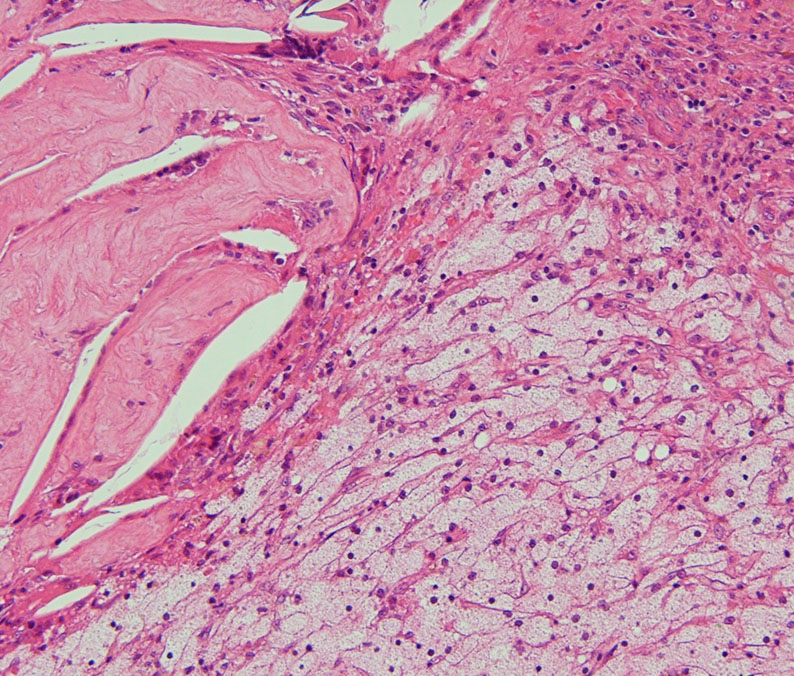

骨化 ossification (まれだけど大切な所見)

A large piece of mature bone in a suprasellar craniopharyngioma.